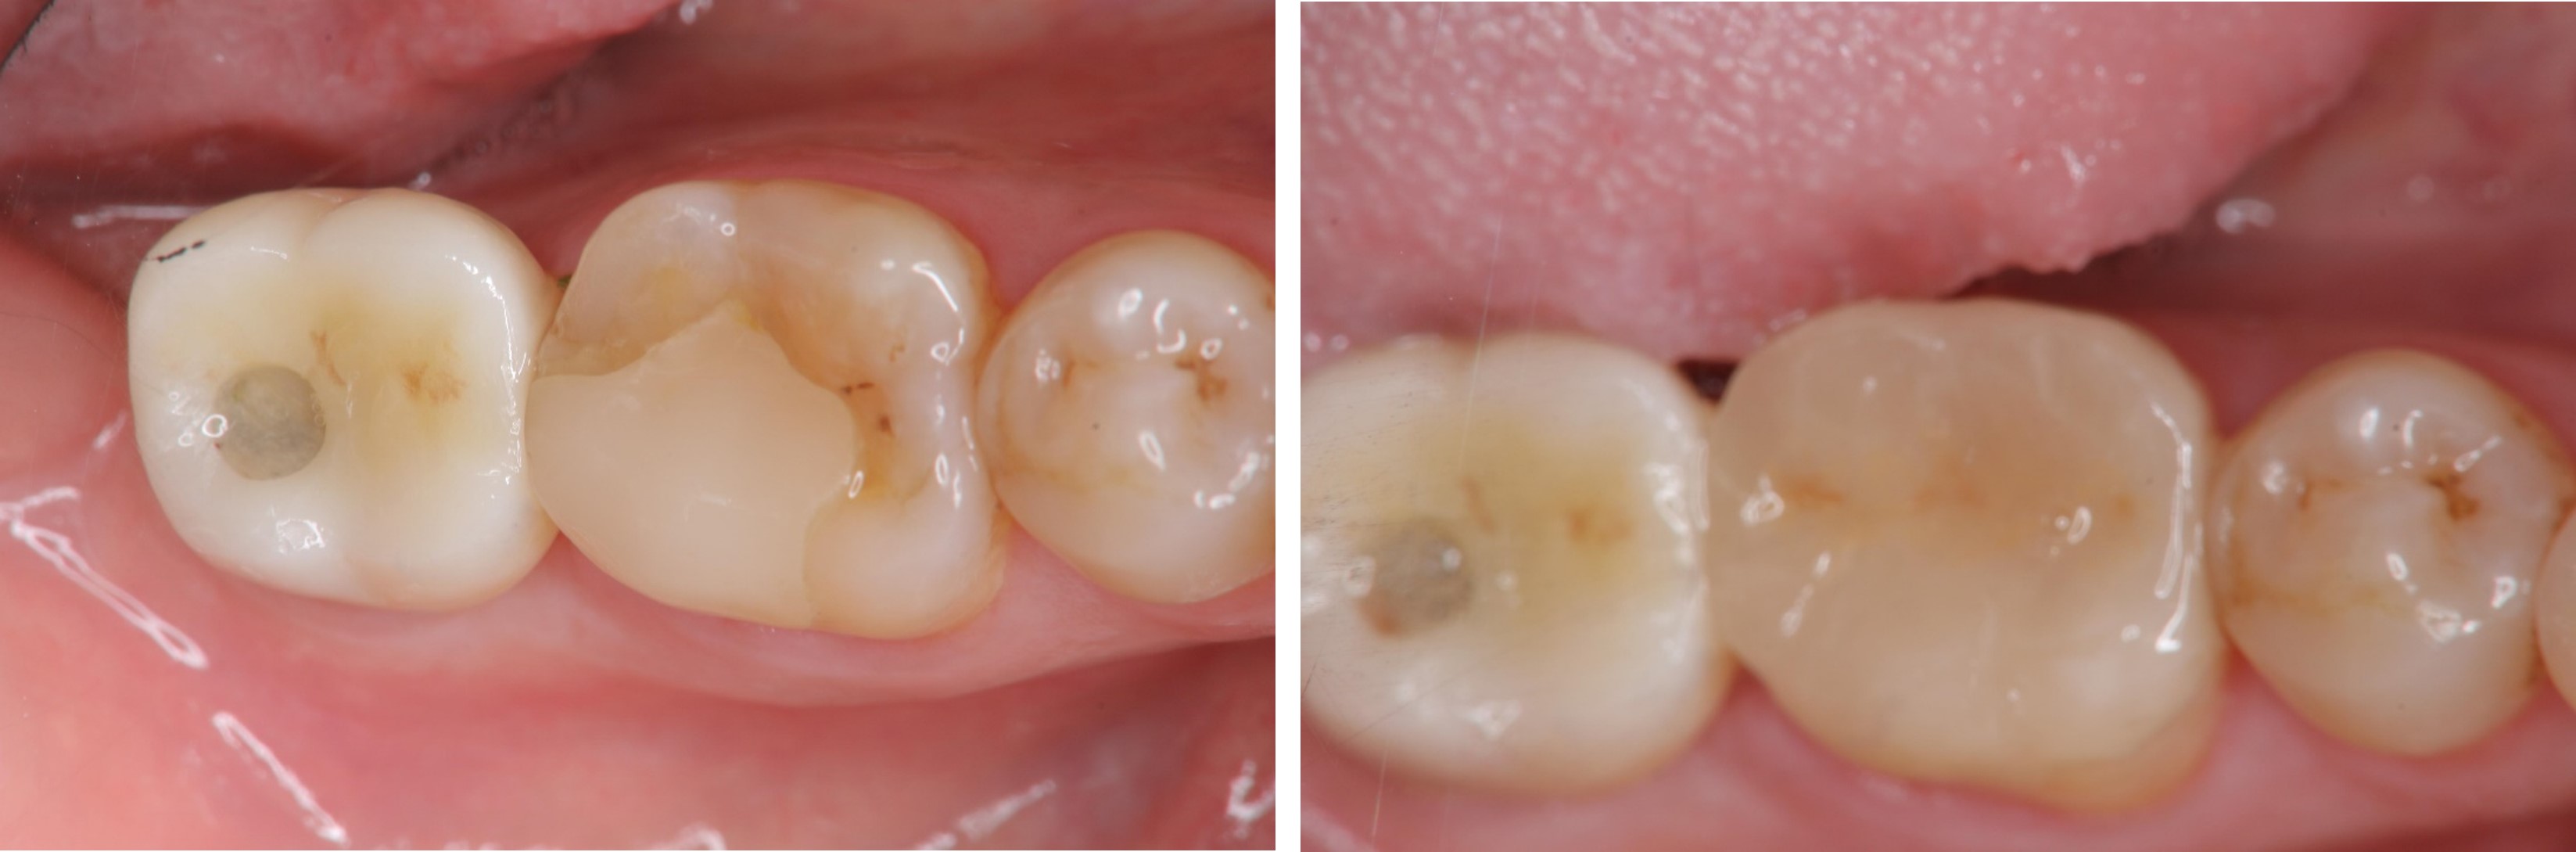

陶瓷冠蓋體-蛀牙-#46

審美牙科

瓷塊-冠蓋體

陶瓷冠蓋體-二次蛀牙-#46